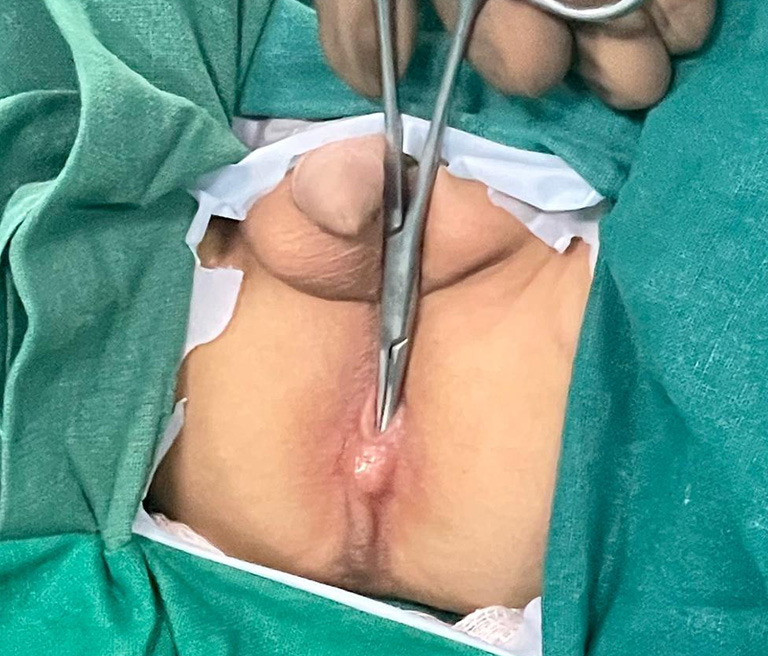

Imperforate Anus

A birth abnormality known as an imperforate anus can develop while your unborn child is still developing in the womb.